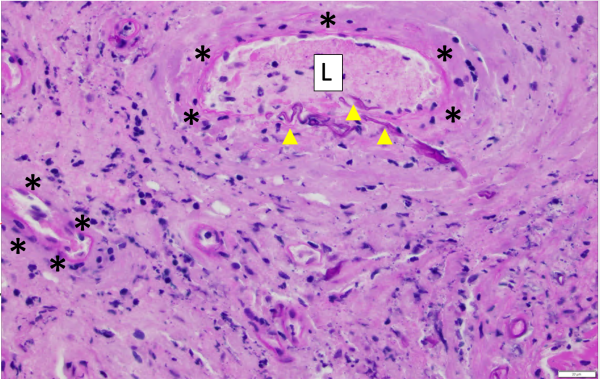

The primary mechanism of spread is through angioinvasion of blood vessels: vasotropic. It causes causes thrombosis, ischemia and disseminates necrosis with poor bleeding. Therefore, frequently in orbital invasion the eye lacks of the typical “hyperemia” (redness) of infection. The angioinvasion also gives the fungus access to additional heme as a source of iron. [7]

One critical step that allows for angioinvasion to occur is the penetration of and damage to the endothelial cells and extracellular matrix proteins lining the blood vessels. One receptor that is known to be involved in the penetration process is a protein known as glucose-regulated protein (GRP78). [7]

Imaging studies may include CT/MRI of orbit, brain, and sinuses demonstrate involvement of maxillary and ethmoid sinus, orbit, cavernous sinus, and less frequently involve the frontal and sphenoid sinus. In order to obtain a true diagnosis of mucormycosis, a fine needle aspiration biopsy of infected tissues must be obtained for histopathology and culture. Characteristic of this disease is aseptate hyphal elements that branch at right angles. [13]

Finally, the gold standard diagnostic procedure is biopsy and culture. Histopathological confirmation included H+E (hematoxylin-eosin), PAS (periodic acid-Schiff) and GMS (Grocott-Gomori's methenamine silver stain), among others.